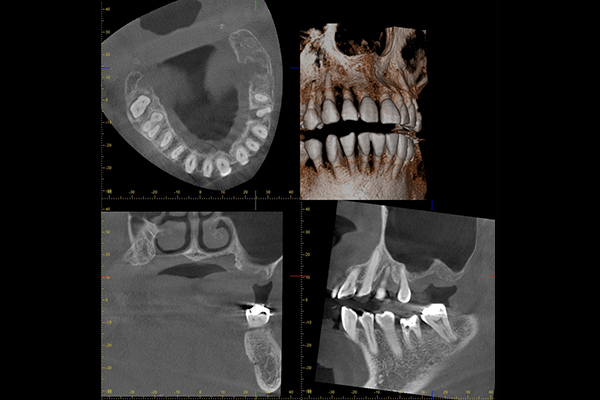

CT撮影

病気の有無、3次元的な根管の形を把握することができます。

正確な診断のためには必須ですが、

保険診療では大臼歯しか撮影することが

できません。

病変や根管の形、状態を3次元的に把握します

通常のレントゲン撮影では確認できない根や、根の先の炎症もCTによって確認することができます。